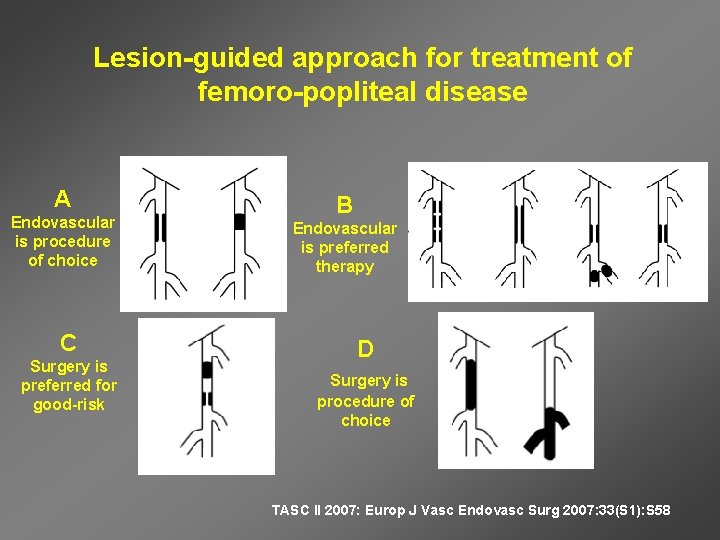

Lesion-guided approach for treatment of femoro-popliteal disease A Endovascular is procedure of choice C Surgery is preferred for good-risk B Endovascular is preferred therapy D Surgery is procedure of choice TASC II 2007: Europ J Vasc Endovasc Surg 2007: 33(S 1): S 58